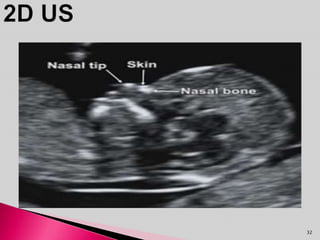

 Absent nasal bone on USG done at 11 to 13

weeks is another marker of Downs syndrome.

 Absence of Nasal bone is not related to NT

and can be combined in one scan.

 Detection rate of DS is 67%.

 When combined with NT detection rate is 90%.